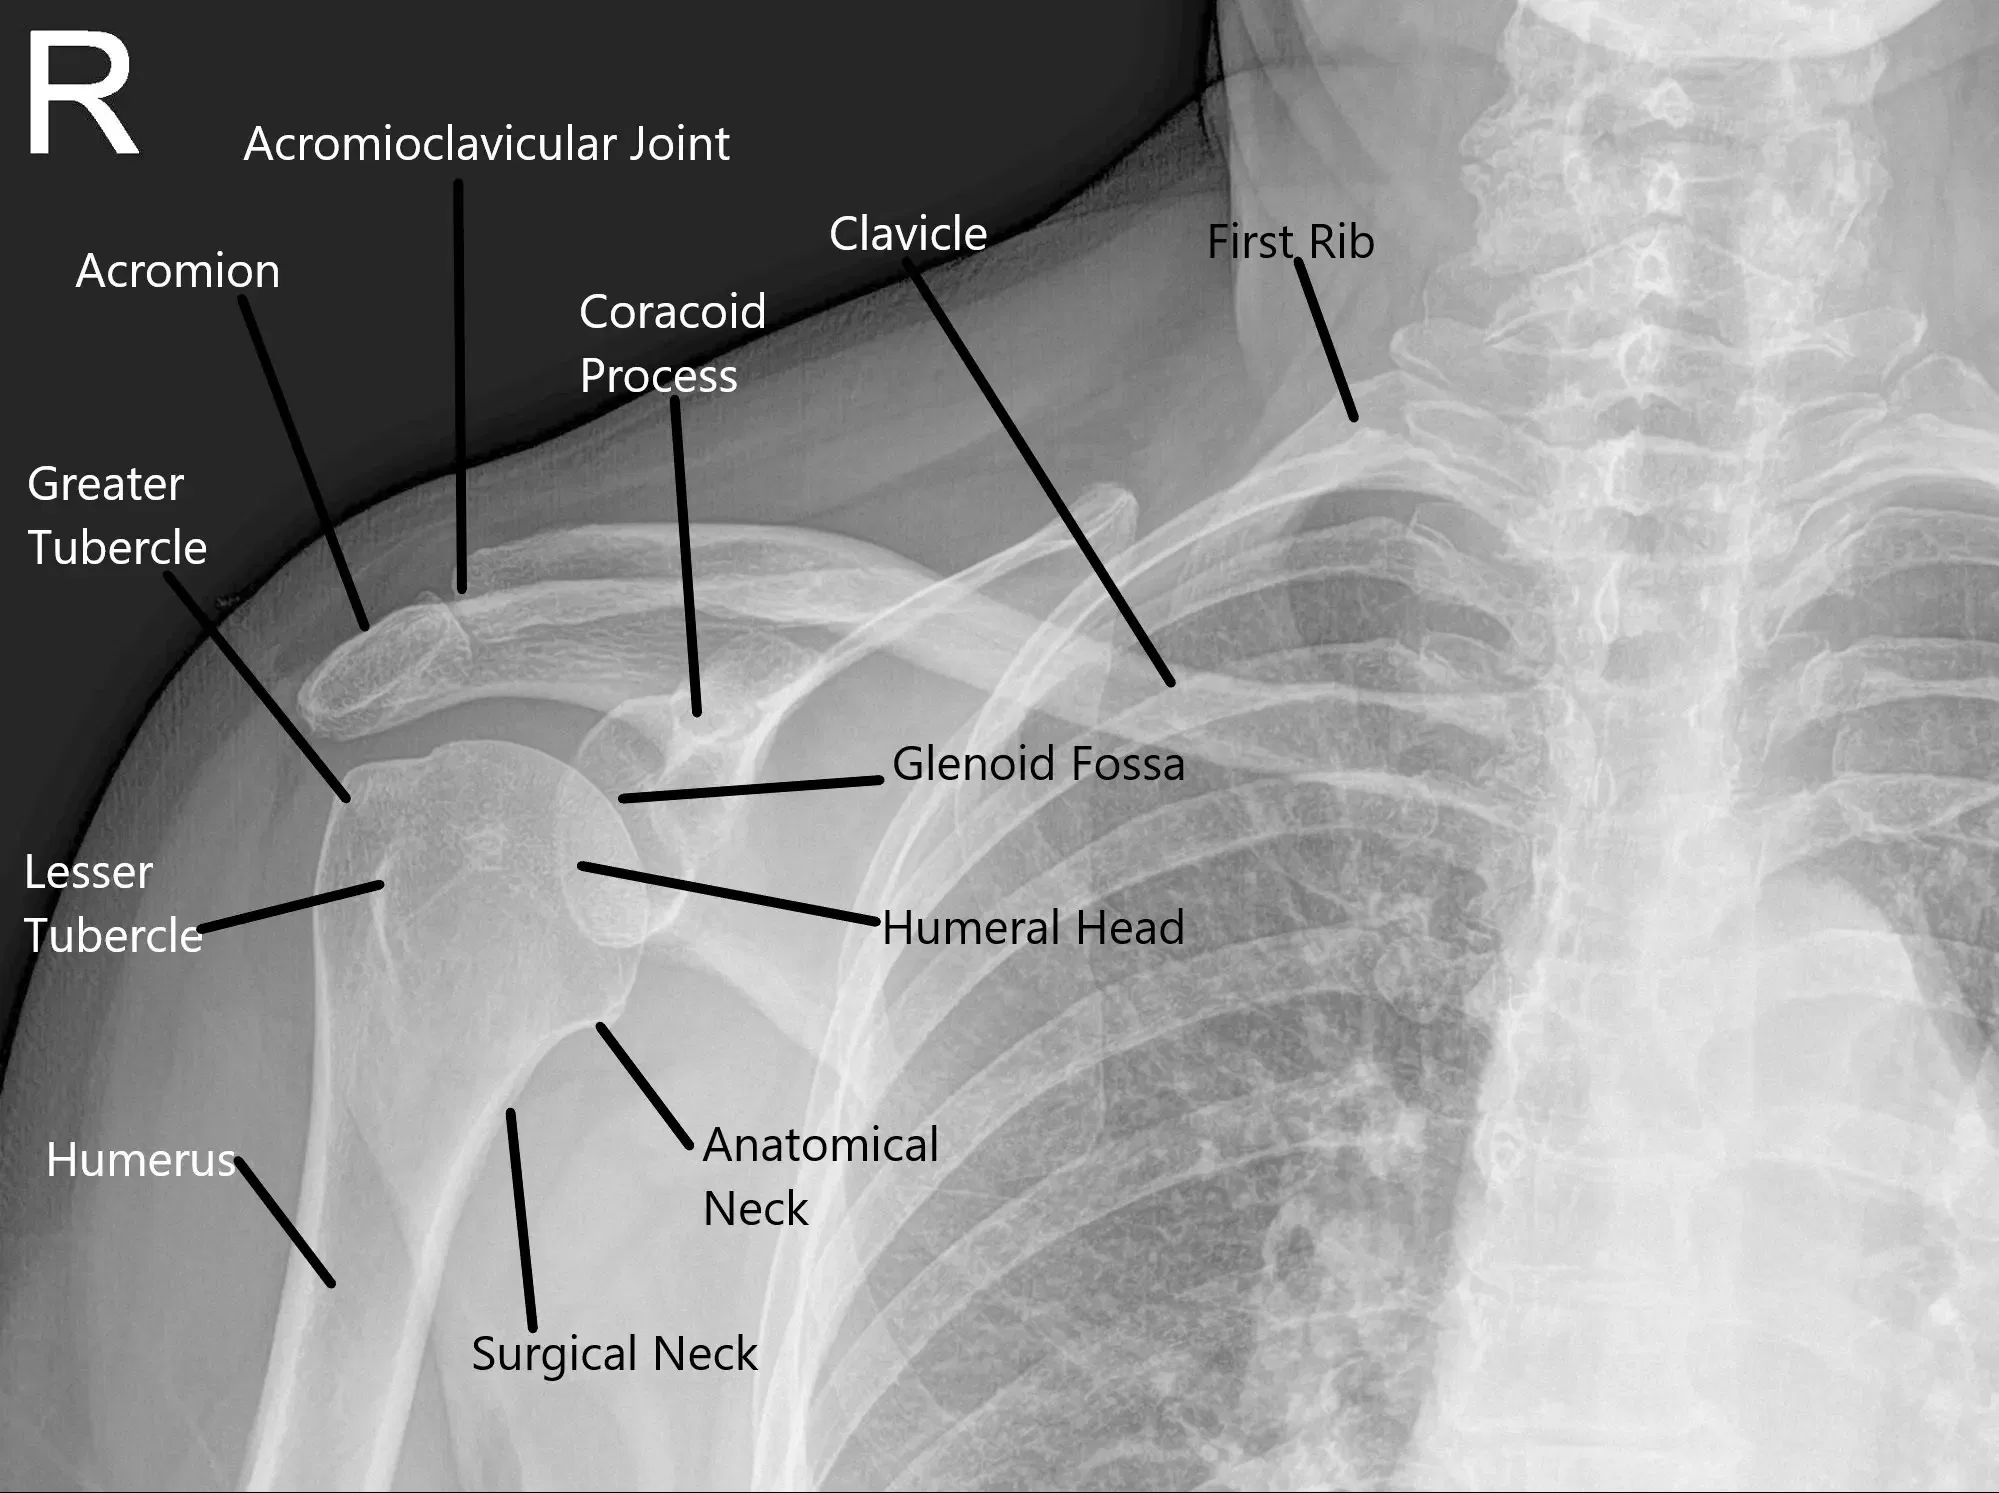

X-Ray of the right shoulder suggested degenerative changes of the acromioclavicular joint.

X-ray showing AP view of the right shoulder.